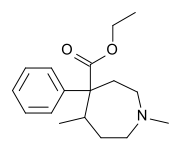

Ketobemidones

Structures